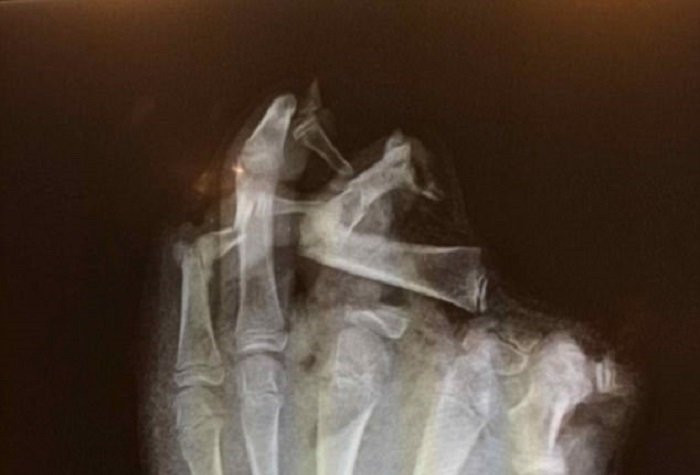

ột bác sĩ đã đăng tải hình ảnh một bàn tay với những khớp xương bị biến dạng lên một diễn đàn y khoa nổi tiếng để tham khảo ý kiến từ các đồng nghiệp.

Được biết, đây là bàn tay của một thanh niên mà ông đang chữa trị, cậu này đã bị thương khi đang chơi pháo trong Đêm hội Bonfire tại Anh.

Cậu thanh niên mất ngón tay do chơi pháo, những gì còn lại chỉ là các khớp giữa ngón tay

Theo như tấm X - quang, cậu thanh niên này có khả năng đã mất đi 3 ngón tay bao gồm ngón cái, ngón trỏ và ngón giữa. Những gì còn lại chỉ là các khớp giữa ngón tay.

Người đứng đầu chương trình giáo dục cấp cứu tại Hội Chữ Thập Đỏ, Joe Mulligan giải thích: "Cậu bé này đã mất hết phần thịt và cơ giữa ngón trỏ và ngón cái”, chấn thương này có thể hoàn toàn làm thay đổi cuộc sống của một con người.